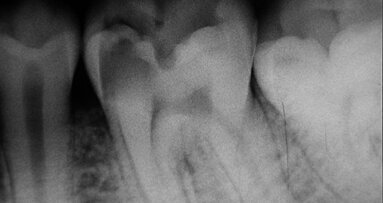

Les 3 mannequins qui ne possèdent pas de corps présentent de vraies dents, et sont exclusivement consacrés à la radiologie. Le « Fantôme haute performance », comme l’appelle Corinne Taddei-Gross, présente quant à lui toutes les fonctions physiologiques d’un être humain. Il est ainsi capable de parler, de s'évanouir, etc. Allongé sur le fauteuil du cabinet, il a tout d’un vrai patient, et peut même exprimer ses souffrances aux étudiants qui procèdent au diagnostic.

Les étudiants de la faculté avaient déjà la possibilité de s’entraîner sur 135 mannequins de simulation mais, selon Corinne Taddei-Gross, « il manquait la possibilité de s’entraîner en radiologie sur des faux patients « en os », comme s’il s’agissait de vrais patients. Nous ne disposions pas non plus de l’équipement nécessaire pour permettre de reproduire des situations de consultations précliniques sur un patient qui réagit ». De plus, les étudiants s’entraînaient entre eux pour la radiologie, s’exposant ainsi aux radiations. Ces quatre mannequins qui disposent de 200 capteurs contribuent désormais à rendre les conditions de formation des étudiants plus efficaces et plus confortables. Le coût de l’opération est de 250 000 euros.